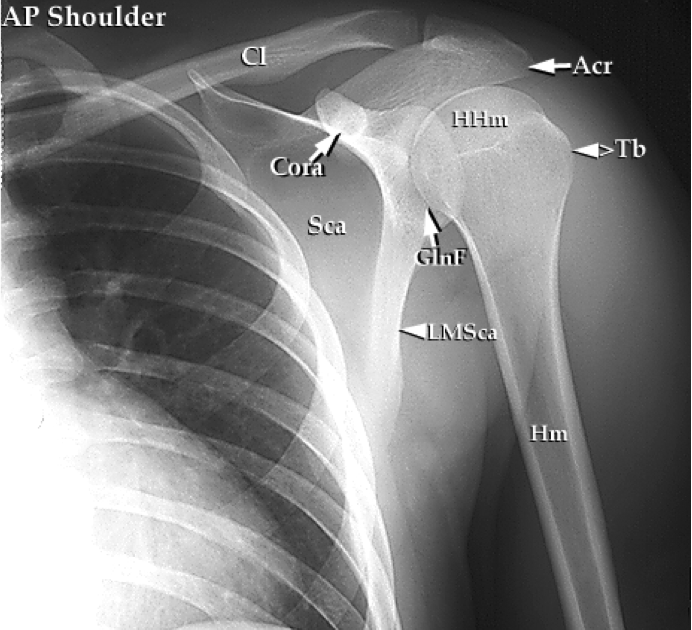

Static Stabilisers Of The Shoulder Complex . For the shoulder complex, dynamic stabilization results in a large range of mobility and. Glenohumeral ligaments (below) glenoid labrum (below) articular congruity and version. shoulder stability is achieved through the interplay of both static and dynamic stabilisers, which work in synchrony to maintain shoulder. — the static and dynamic stabilizers of the shoulder can be classified as passive and active mechanisms for. — [2] [5] the static and dynamic stabilizing structures allow for extreme degrees of motion in multiple planes of the body that predisposes. — static restraints. — 8.3.2 dynamic stability. stabilizers of the shoulder. — soft tissue stabilizers, bone morphology and dynamic stabilizers such.